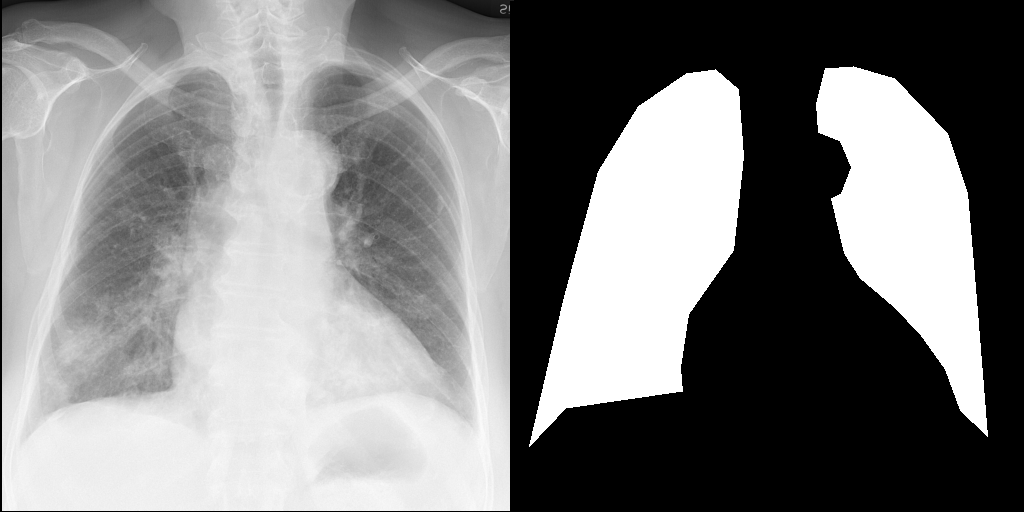

Let's load an example image of a patient with influenza.

import requests

from PIL import Image, ImageDraw

from torchvision import transforms

def download_sample_image() -> Image.Image:

"""Download chest X-ray with CC license."""

base_url = "https://upload.wikimedia.org/wikipedia/commons"

image_url = f"{base_url}/2/20/Chest_X-ray_in_influenza_and_Haemophilus_influenzae.jpg"

headers = {"User-Agent": "RadEdit"}

response = requests.get(image_url, headers=headers, stream=True)

return Image.open(response.raw)

image = download_sample_image()

input_image = transforms.Compose([transforms.Resize(512), transforms.CenterCrop(512)])(image)

right_lung_coords = [(19, 445), (53, 299), (88, 170), (128, 105), (176, 72), (205, 68), (228, 88), (233, 155), (223, 249), (178, 313), (170, 366), (172, 390), (55, 407)]

left_lung_coords = [(477, 435), (466, 298), (457, 192), (437, 132), (384, 77), (343, 65), (315, 67), (306, 102), (308, 131), (330, 140), (341, 166), (331, 192), (321, 197), (334, 252), (350, 277), (383, 305), (410, 333), (435, 368), (450, 409)]

# Create a blank image with the same size as the original image

lung_mask = Image.new("L", (512, 512), 0)

# Draw the filled shape using the coordinates

draw = ImageDraw.Draw(lung_mask)

draw.polygon(right_lung_coords, fill=255)

draw.polygon(left_lung_coords, fill=255)

For this example, we will remove the visual appearance of influence from the lungs, while preventing changes from happening to the rest of the image. To do this, we create a mask of the lung regions and use this as the edit_mask which defines the region we wish the editing prompt to be applied to. Since we want the rest of the image to remain unchanged, we use the inverse as the keep_mask which defines the region where edits are discouraged from taking place.

from PIL import ImageOps

edit_mask = lung_mask

keep_mask = ImageOps.invert(lung_mask)